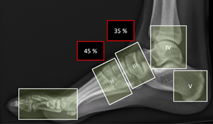

The patient was referred to an orthopedic specialist and plain radiography of the feet was performed, though not weight-bearing images (Figure 4).

Figure 4 Plain radiography of dorsoplantar images of both feet (A: orange arrow shows degeneration of the right naviculocuneiform joint with collapse; star sign shows unclear image borders of the left cuneiform and cuboid bones; blue arrow shows consolidated fracture of the left 5th metatarsal); lateral image of right foot (B: star sign shows unclear margins of the cuneiform bones; blue arrow shows signs of bone absorption of the cuboid bone borders); and lateral image of left foot (C: blue arrow shows unclear margins of the cuneiform bones; orange arrow shows consolidated fracture of the 5th metatarsal). NOTE: the images are not in a loading position.

Foot radiography already demonstrated bilateral Charcot feet, although on examination, only the right foot showed clinical signs of foot deformity. Bilateral tarsal bones showed signs of osteolysis on radiography and, overall, left foot radiography looked worse when compared to the right foot radiography. No other imaging technique was performed.  Literature has documented that 10 to 30% of the patients with Charcot foot have bilateral incidence.1,3,5,7,8 It might be probably 30% or more because these patients usually have difficulty controlling their diabetes and complying with the offloading therapy, consequently overloading the contralateral body, and accelerate foot degeneration.